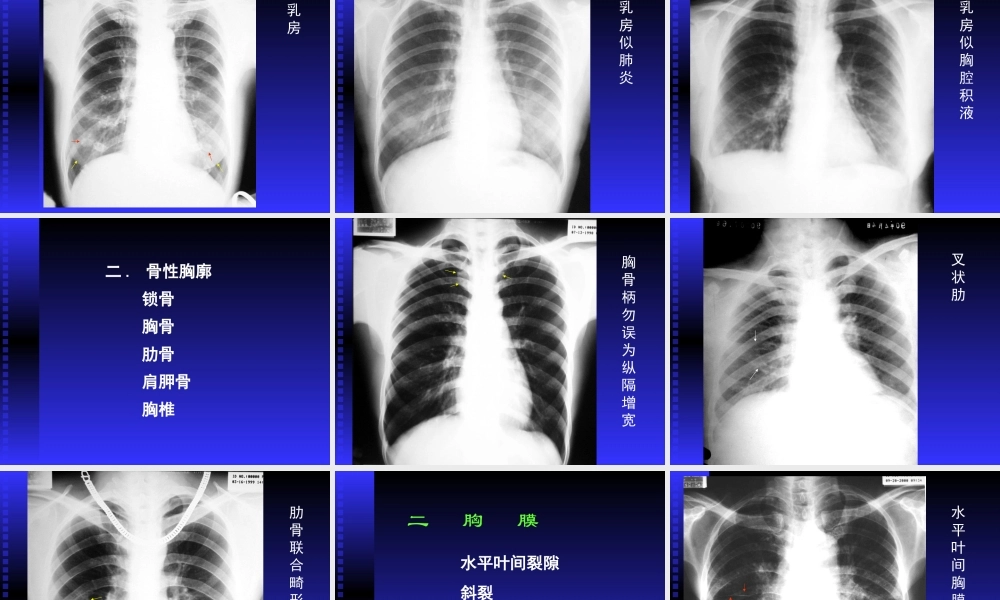

胸部影像诊断学呼吸系统第一节影像学检查方法1、透视2、摄片3、高仟伏摄影4、体层5、支气管造影6、血管造影7、CT、MRI8、超声透视时,荧光屏上的影像以黑色表示高密度物质;以白色透亮表示低密度物质正位胸片侧位胸片高千伏摄影使气管内病变显示(气管癌)支气管造影GUIYANGMEDICALCOLLEGEGUIYANGMEDICALCOLLEGECT用于胸部检查,可根据需要,调节窗宽窗位,显示不同内容第二章正常胸部影像学表现思考重点:能在X线胸片上留下影像的胸壁软组织有哪些?壹胸廓一.胸壁软组织胸锁乳突肌锁骨上皮肤皱折胸大肌乳房和乳头胸锁乳突肌和锁骨上皮肤皱折胸大肌肩胛骨和乳头乳房乳房似肺炎乳房似胸腔积液二.骨性胸廓锁骨胸骨肋骨肩胛骨胸椎胸骨柄勿误为纵隔增宽叉状肋肋骨联合畸形二胸膜水平叶间裂隙斜裂叶间胸膜(细线状致密影)水平叶间胸膜三膈肌位置运动升高或降低原因波浪膈心膈角肋膈角心膈角后肋膈角波浪膈侧肋膈角前肋膈角后肋膈角正常膈肌和各肋膈角、心膈角波浪膈四肺肺叶(肺段、肺小叶、肺腺泡)气管与支气管肺实质肺间质肺野思考重点:解释下列名词:肺实质肺间质肺野肺门肺门角肺纹理一肺实质肺内具有气体交换功能的所有含气腔隙及结构。包括肺泡、肺泡壁、肺泡管和末梢呼吸细支气管影像表现为含气的透亮影二肺间质肺内由纤维结缔组织构成的肺实质的支撑结构和间隙。包括肺泡外壁和肺泡与肺泡之间、肺泡与胸膜之间、肺泡与血管、支气管之间的间隙肺间质一般不留下影像,但可见到在肺间质中走行的肺血管影像显示肺间质和肺实质示意图三肺野胸部影像上,肺部所有表现为透亮影像的部分,包括肺实质和正常的肺间质。两侧肺野透亮度应一致肺野分为:1上野、中野、下野2内带、中带、外带四肺门进出于纵隔与肺之间的各种组织结构肺门的影像主要由肺动脉和肺静脉构成表现为中肺野内带的、粗大的条索状影像肺门角右上肺门和下肺门的血管影像之间形成的夹角左肺动脉弓左肺动脉分出后急剧转向下方,形成的弓状弧形影左侧无肺门角箭头指示肺门角和左肺动脉弓五肺纹理是肺门组织结构进入肺内的延续形成影像的主要是肺动脉分支影像表现为:自肺门向肺野呈放射分布的干树枝状影肺纹理肺纹理:自肺门向肺野呈干树枝样分布的条索状影像,至外带基本消失。粗细多少因个体差异而明显不同CT图像上肺纹理仍为干树枝样条索状密影五纵隔位于两肺之间、胸骨之后、胸椎之前。其内包含心脏、主动脉、气管、主支气管、食管、神经组织、淋巴、脂肪、结缔组织等正位胸片上位置...